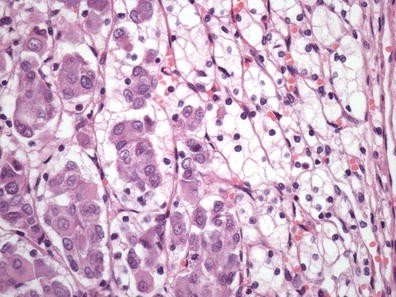

Objective: Cell distribution and cell density are the main characteristic for tumor pathology. We do not yet understand how many cells inhabit a tumor from a 1 sq mm sample of histology slide. We analyzed a total number of tumor cells in breast cancer; renal cell carcinoma; lung carcinoma (NSC), and endometrial carcinoma and proliferative activity (% Ki67-positive cells) to establish the precise quantity of tumor cells per sq.mm of histological slide and the relations of this measure with proliferation.

Method: The study included 46 breast carcinomas; 44 RCC; 21 NSCLC, and 35 endometrial carcinoma.

Results: Mean absolute tumor cells in 1 mm2 of histology slide was for breast cancer: 4,160+/−251, Ki67–31 %; NSCL: 4,102+\\− 364 cells, Ki67–15 %; endometrial carcinoma: 7,073+\\− 614, Ki67–31.9 %; RCC 4,389+\\− 229, Ki67 11.62 %. There was moderate correlation between cell density and Ki67 for breast cancer r = 0.42 (p = 0.00018); for NSCL, r = 0,41 (p = 0,0,032), for endometrial carcinoma r = 0,48 (p = 0,0,059) and no correlation for RCC.

Conclusion: By analysis of these four types of cancer was established the quantity of tumor cells per mm2 and main the proliferative characteristics